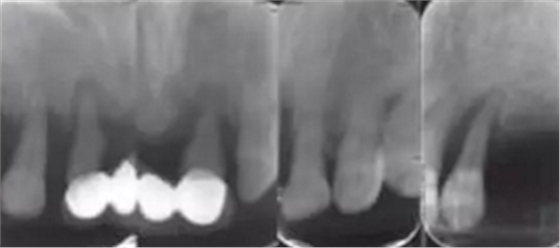

影像學(xué)檢查:下頜修復(fù)體與種植體邊緣密合,種植體周圍并無明顯異常,14、13、21、22、24、25見根尖陰影,牙槽骨吸收至根尖1/3。23見牙周膜增寬影,牙槽骨吸收至根中1/2(圖2,3)。診斷:上頜牙列缺損(15、16、17、26、27缺失);上頜廣泛性重度牙周炎;14、13、21、22、25根尖周炎。

圖2 術(shù)前根尖片檢查